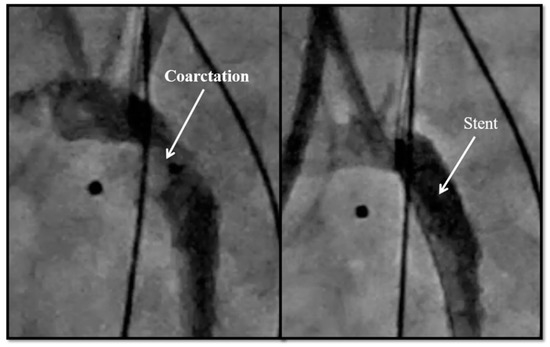

| 5. Coarctation of the aorta stent | 6 |

| 5. Coarctation of the aorta stent | 6 | 0 | 1 | 3 |